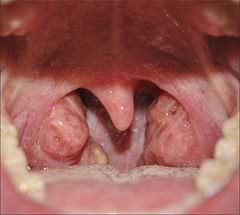

Дырки в миндалинах — фото

Чем опасны дырки в миндалинах

Многие люди, обнаружившие отверстия на гландах, понимают, что это патология, но не придают ей особого значения, до тех пор, пока горло их не беспокоит. Это неправильно, поскольку наличие дырок в горле разрушает защитный механизм, а также позволяет болезнетворным микробам свободно размножаться. Даже при незначительном воспалении могут наблюдать следующие явления:

- Скопление гнойных масс, которые при осмотре горла выглядят, как белые пятна на миндалинах.